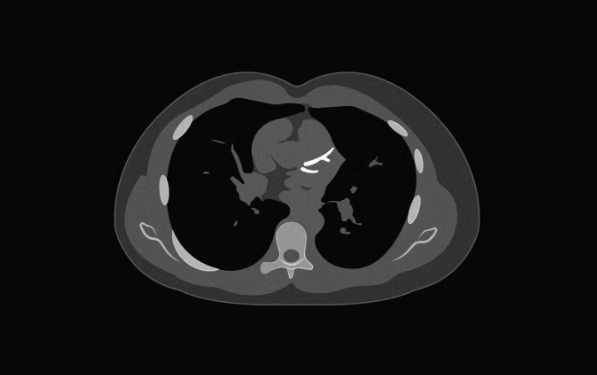

Bëhet fjalë për skanimin e kalciumit në arteriet koronare, i njohur si Coronary Artery Calcium scan, i cili mat nivelin e depozitave të kalciumit në arteriet e zemrës. Rezultatet e këtij testi variojnë nga 0 deri në 1,000 dhe po përdoren gjithnjë e më shumë nga mjekët për të përcaktuar rrezikun e pacientëve dhe nevojën për trajtim me ilaçe për kolesterolin.